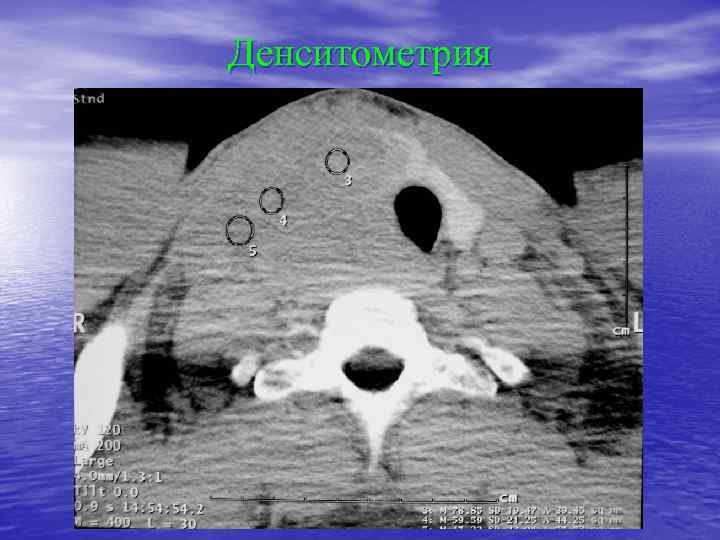

Денситометрический анализ Определение основных видов патологических образований: - обызвествленных - мягкотканных - жидкостных - жиросодержащих - воздухсодержащих

Денситометрия